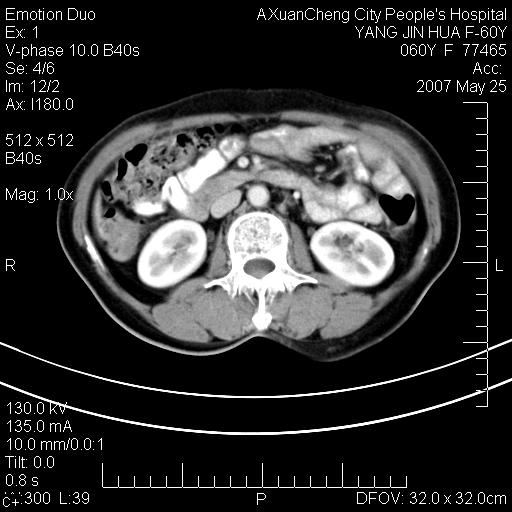

左背部皮下良性肿瘤,密度不均,边界不清,内有脂肪、钙化,增强扫描无明显强化,血管平滑肌脂肪瘤?进一步诊断有困难,建议穿刺活检。

左侧背部皮下混杂密度肿块,结构较疏松,边缘欠光整,内有多发斑点状钙化,考虑:皮下血管瘤。

左背部皮下良性肿瘤,密度不均,边界不清,内有脂肪、钙化,增强扫描无明显强化,血管平滑肌脂肪瘤?进一步诊断有困难,建议穿刺活检。还有,我想还是问一下病史,患者有外伤史吗?能否完全排除外伤后机化的....

血管平滑肌脂肪瘤,支持!另应详细了解病史,待除外骨化性肌炎。

1.考虑左腰部皮下平滑肌脂肪瘤可能性大;

2.位置特殊,不除外畸胎瘤及错构瘤可能;

3.另骨化性肌炎应在考虑范围之内,请追问病史;

还是考虑皮下血管瘤,强化不明显可能跟大量血栓形成有关,好多战友考虑血管平滑肌脂肪瘤,血管平滑肌脂肪瘤的血管就不强化么?只要有血管就都应该强化。